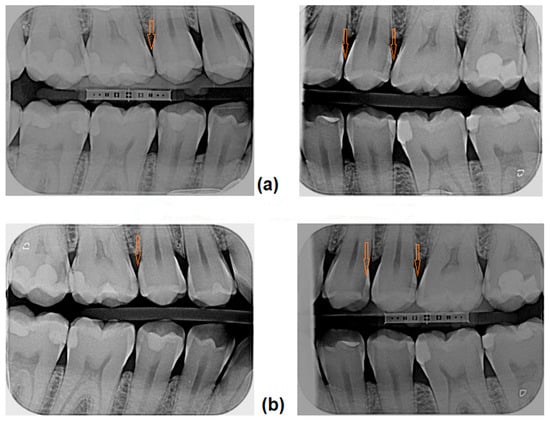

The infiltration protocol included (Figure 1):

• cleaning the tooth and isolating it with a rubber dam (MiniDam, DMG, Germany), placing a wedge (included in Icon Proximal, DMG, Germany) to separate the teeth;

• etching the tooth surface—Icon Etch (15% HCl) for 2 min;

• rinsing with water for 30 s and drying;

• application of Icon Dry (99% ethanol) for 30 s, followed by air drying;

• application of Icon Infiltrant (TEGDMA) for 3 min, removal of excess and light-curing for 40 s;

• reapplication of Icon Infiltrant for 1 min, followed by light-curing for 40 s;

• polishing.

Figure 1. Resin infiltration: (A) tooth isolation and separation; (B) etching with 15% hydrochloric acid—Icon Etch for 2 min; (C) drying with pure alcohol—Icon Dry for 30 s; (D) infiltration with Icon Infiltrant for 3 min, light-curing and second infiltration for 1 min.